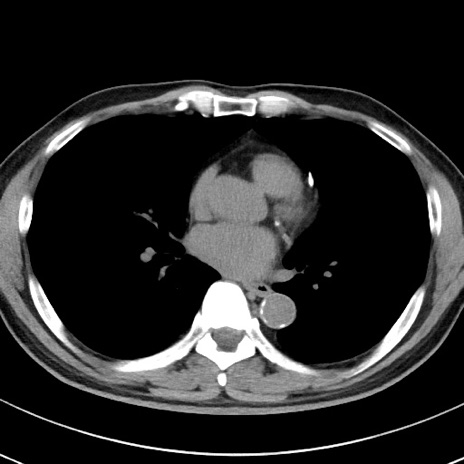

【腹部TIPS】症例29 参考症例 CT(横断像)

症例

70歳代男性